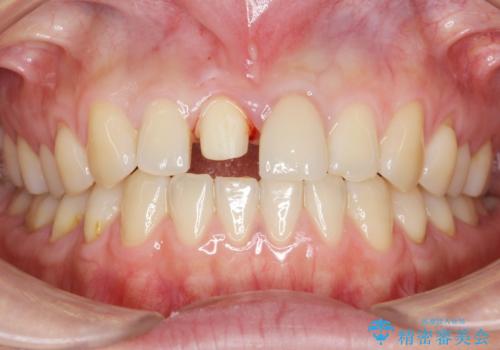

- 右上の前歯が折れたことを主訴に来院された患者様です。

歯が折れた部分は他院により応急処置で仮止めされていました。

欠けた範囲が大きかったため、セラミッククラウンによる補綴治療を行いました。

※左上の前歯(外国で治療されたとのこと)の失活が疑われたためそちらの治療も提案しましたが、ご希望されませんでした。